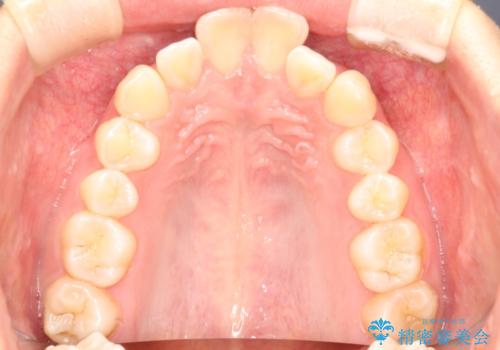

前歯の突出、深い噛み合わせ、ガタつきをマウスピース矯正(インビザライン)で治療した症例

- 初診時には上顎前歯の突出、前歯部の深いかみ合わせ、叢生が見られる状態でした。

使用したインビザラインのマウスピース枚数:42枚+25枚+22枚(初回マウスピース+リファインメントが2回、1週間に1枚ペースでの交換)

このケースでは非抜歯にて奥歯を後方に移動させる事で前歯の突出を改善するスペースを作り出していますが、これはマウスピースと顎間ゴムの併用によるもので、患者様のご協力の賜物と言えます。

深い噛み合わせについてはシミュレーション上の結果と、予期される実際の歯の移動量とを考慮し、特殊なセットアップを行う事で望ましい結果を得ることができました。

治療途中でリファインメントという追加のマウスピースを製作する手順を行っていますが、その際に上下の正中を合わせたいとの要望があったため、追加シミュレーションの際に追加でセットアップを施しましたが、無事、上下の正中もご要望通りに改善しています。